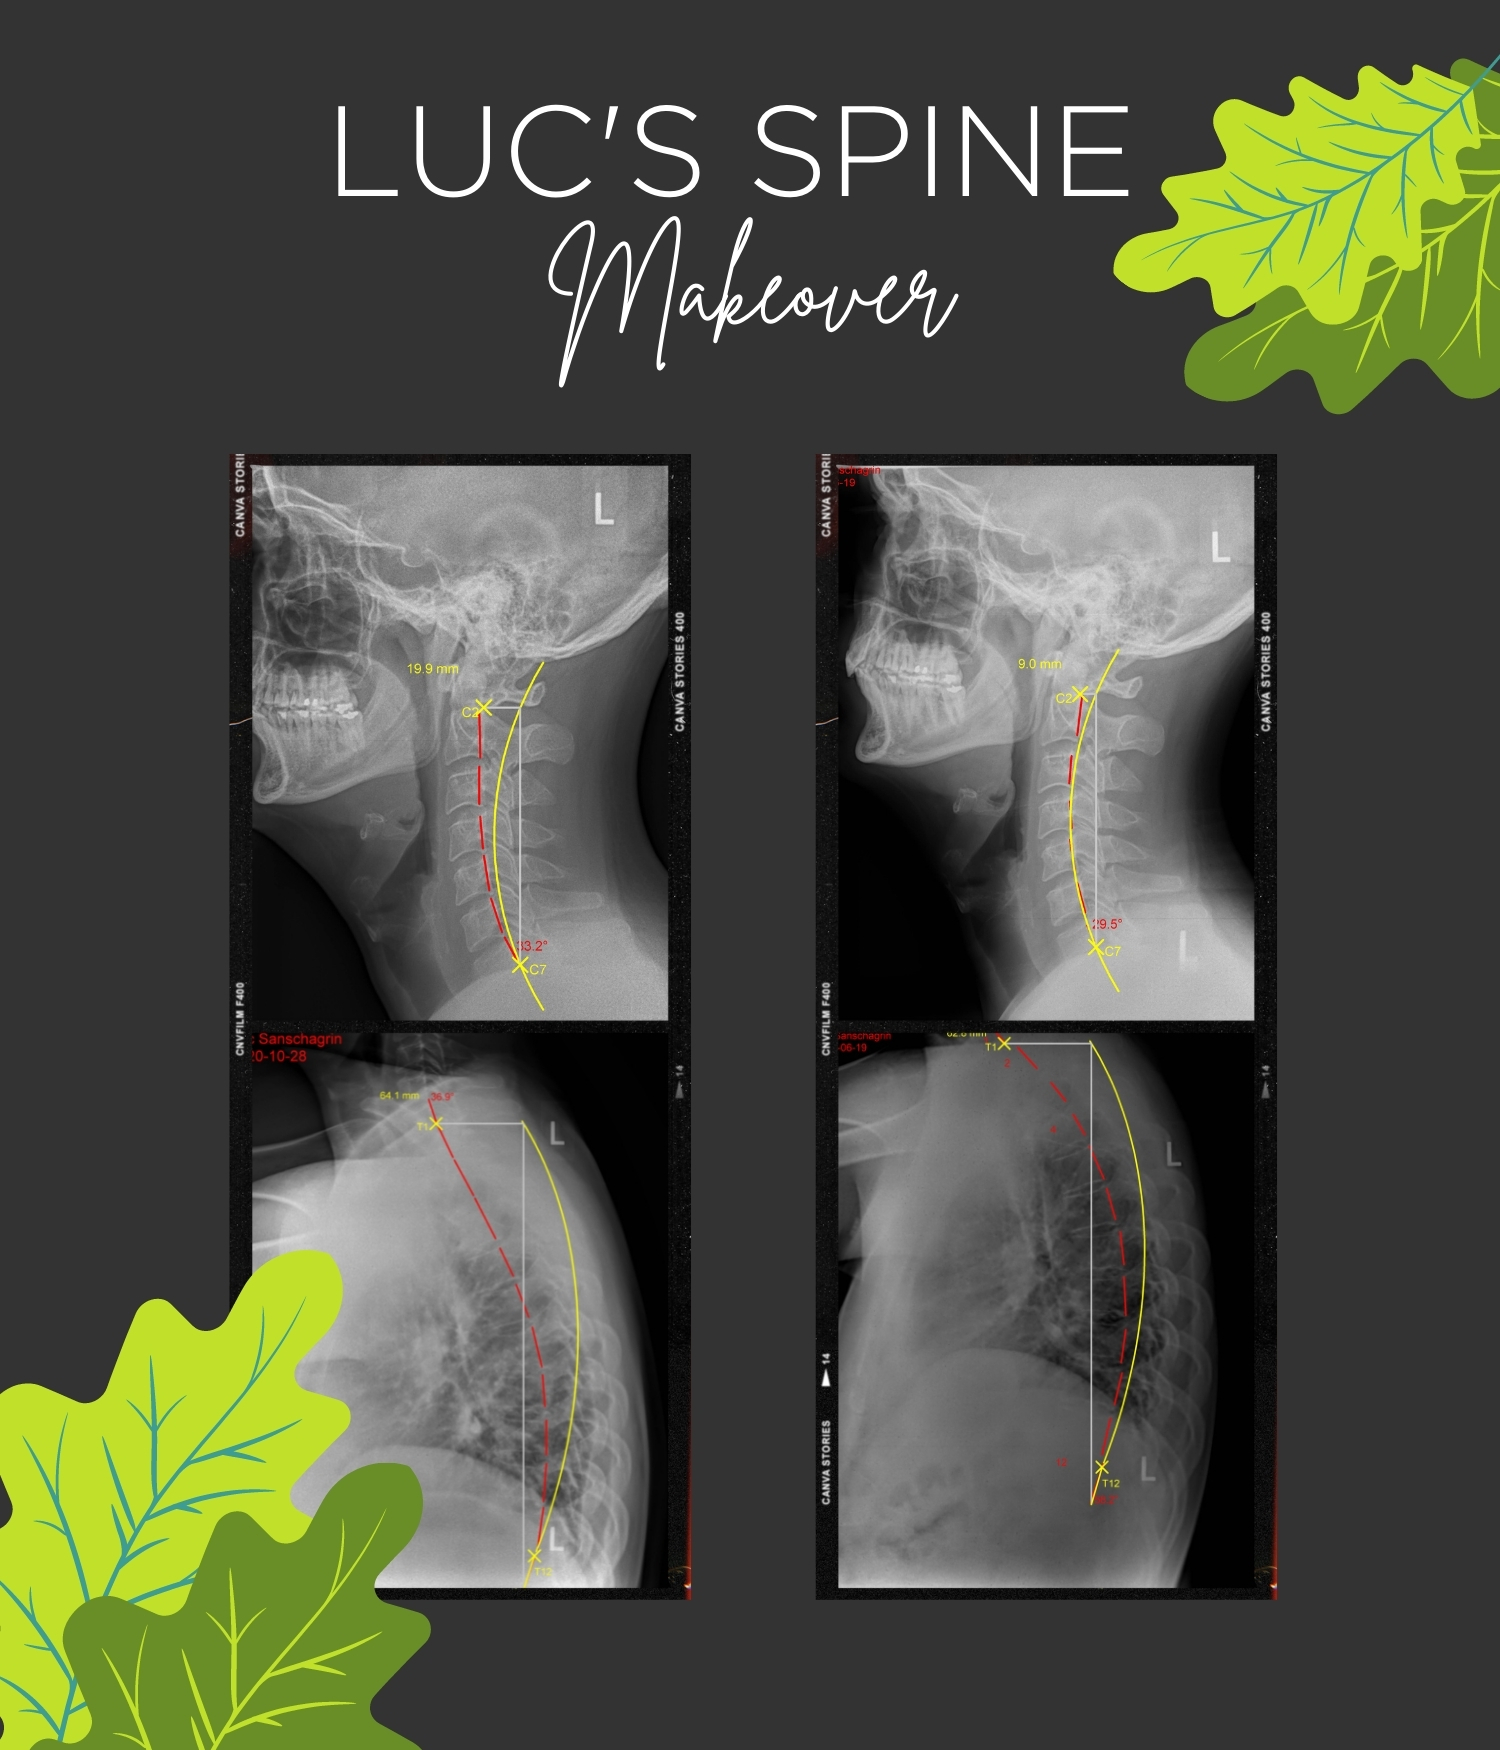

Congratulations to our Spine makeover winner Luc! He has been receiving corrective chiropractic care for over 6 months at the clinic and has had amazing results!

Luc was excited to win as his wife and child have been patients for years with great results. As a bus driver, he had been suffering with mid back and shoulder pain for years and unsure how to correct it. He now reports no pain and better function overall!

At Oaktree we focus not only on helping improve function and reduce pain, but actually getting to the source of why the pain is there. Take a look at Luc’s pre and post X-rays and you’ll see he’s really improving!